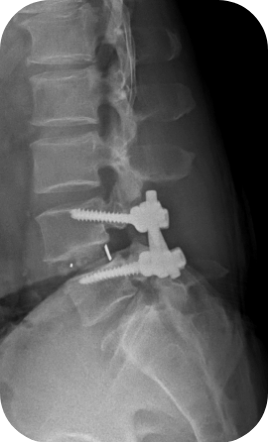

척추유합술(피질골 나사못을 이용한 유합술)

척추 분절의 불안정성이 확인 되면 나사못과 뼈유합을 이용한 고정술이라는 수술을 택할 수 있습니다. 일반적으로 큰 수술이고 긴 시간과 많은 출혈량이 문제이지만 저희 좋은 아침병원에서 시행되는 유합술은 부분마취하 최소침습의 방법으로 빠른 회복과 부작용의 최소화에 힘쓰고 있습니다.